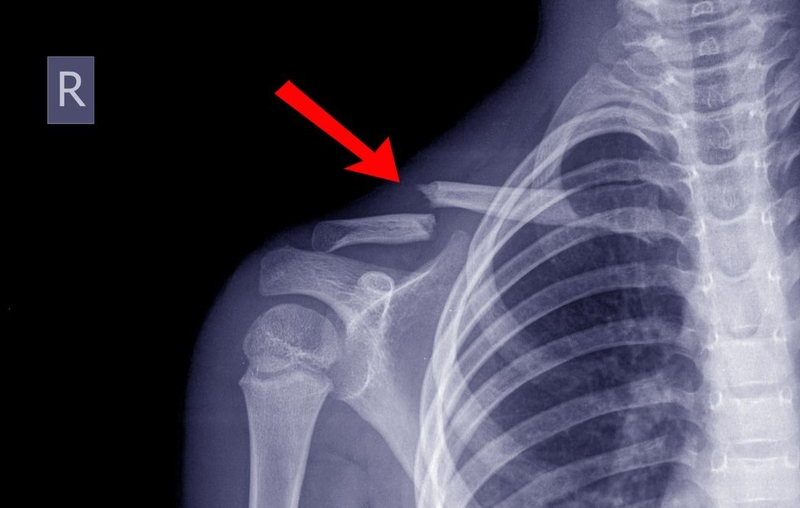

Xương đòn còn gọi là xương quai xanh là một xương dài nằm dưới da vùng vai, nối giữa xương ức và hệ thống đai vai – cánh tay. Nó có tác dụng như một thanh chống, giằng giữa thân mình và khớp vai, giúp khớp vai hoạt động hiệu quả. Trong nhiều trường hợp, xương đòn có thể bị gãy.

Gãy xương đòn được xử lý bằng cách nẹp vít xương đòn hay còn gọi là phẫu thuật kết hợp xương bằng nẹp vít. Mục đích là để giữ xương cố định giúp quá trình lành xương diễn ra nhanh chóng, thuận lợi hơn. Mổ tháo nẹp vít xương đòn là một thủ thuật y khoa nhằm loại bỏ các nẹp vít đã được sử dụng để cố định xương đòn bị gãy trước đó. Khi xương đòn bị gãy đã hồi phục hoàn toàn, nẹp vít sẽ không còn cần thiết và có thể được tháo ra. Việc này giúp giảm thiểu cảm giác khó chịu hoặc đau đớn do nẹp vít gây ra.